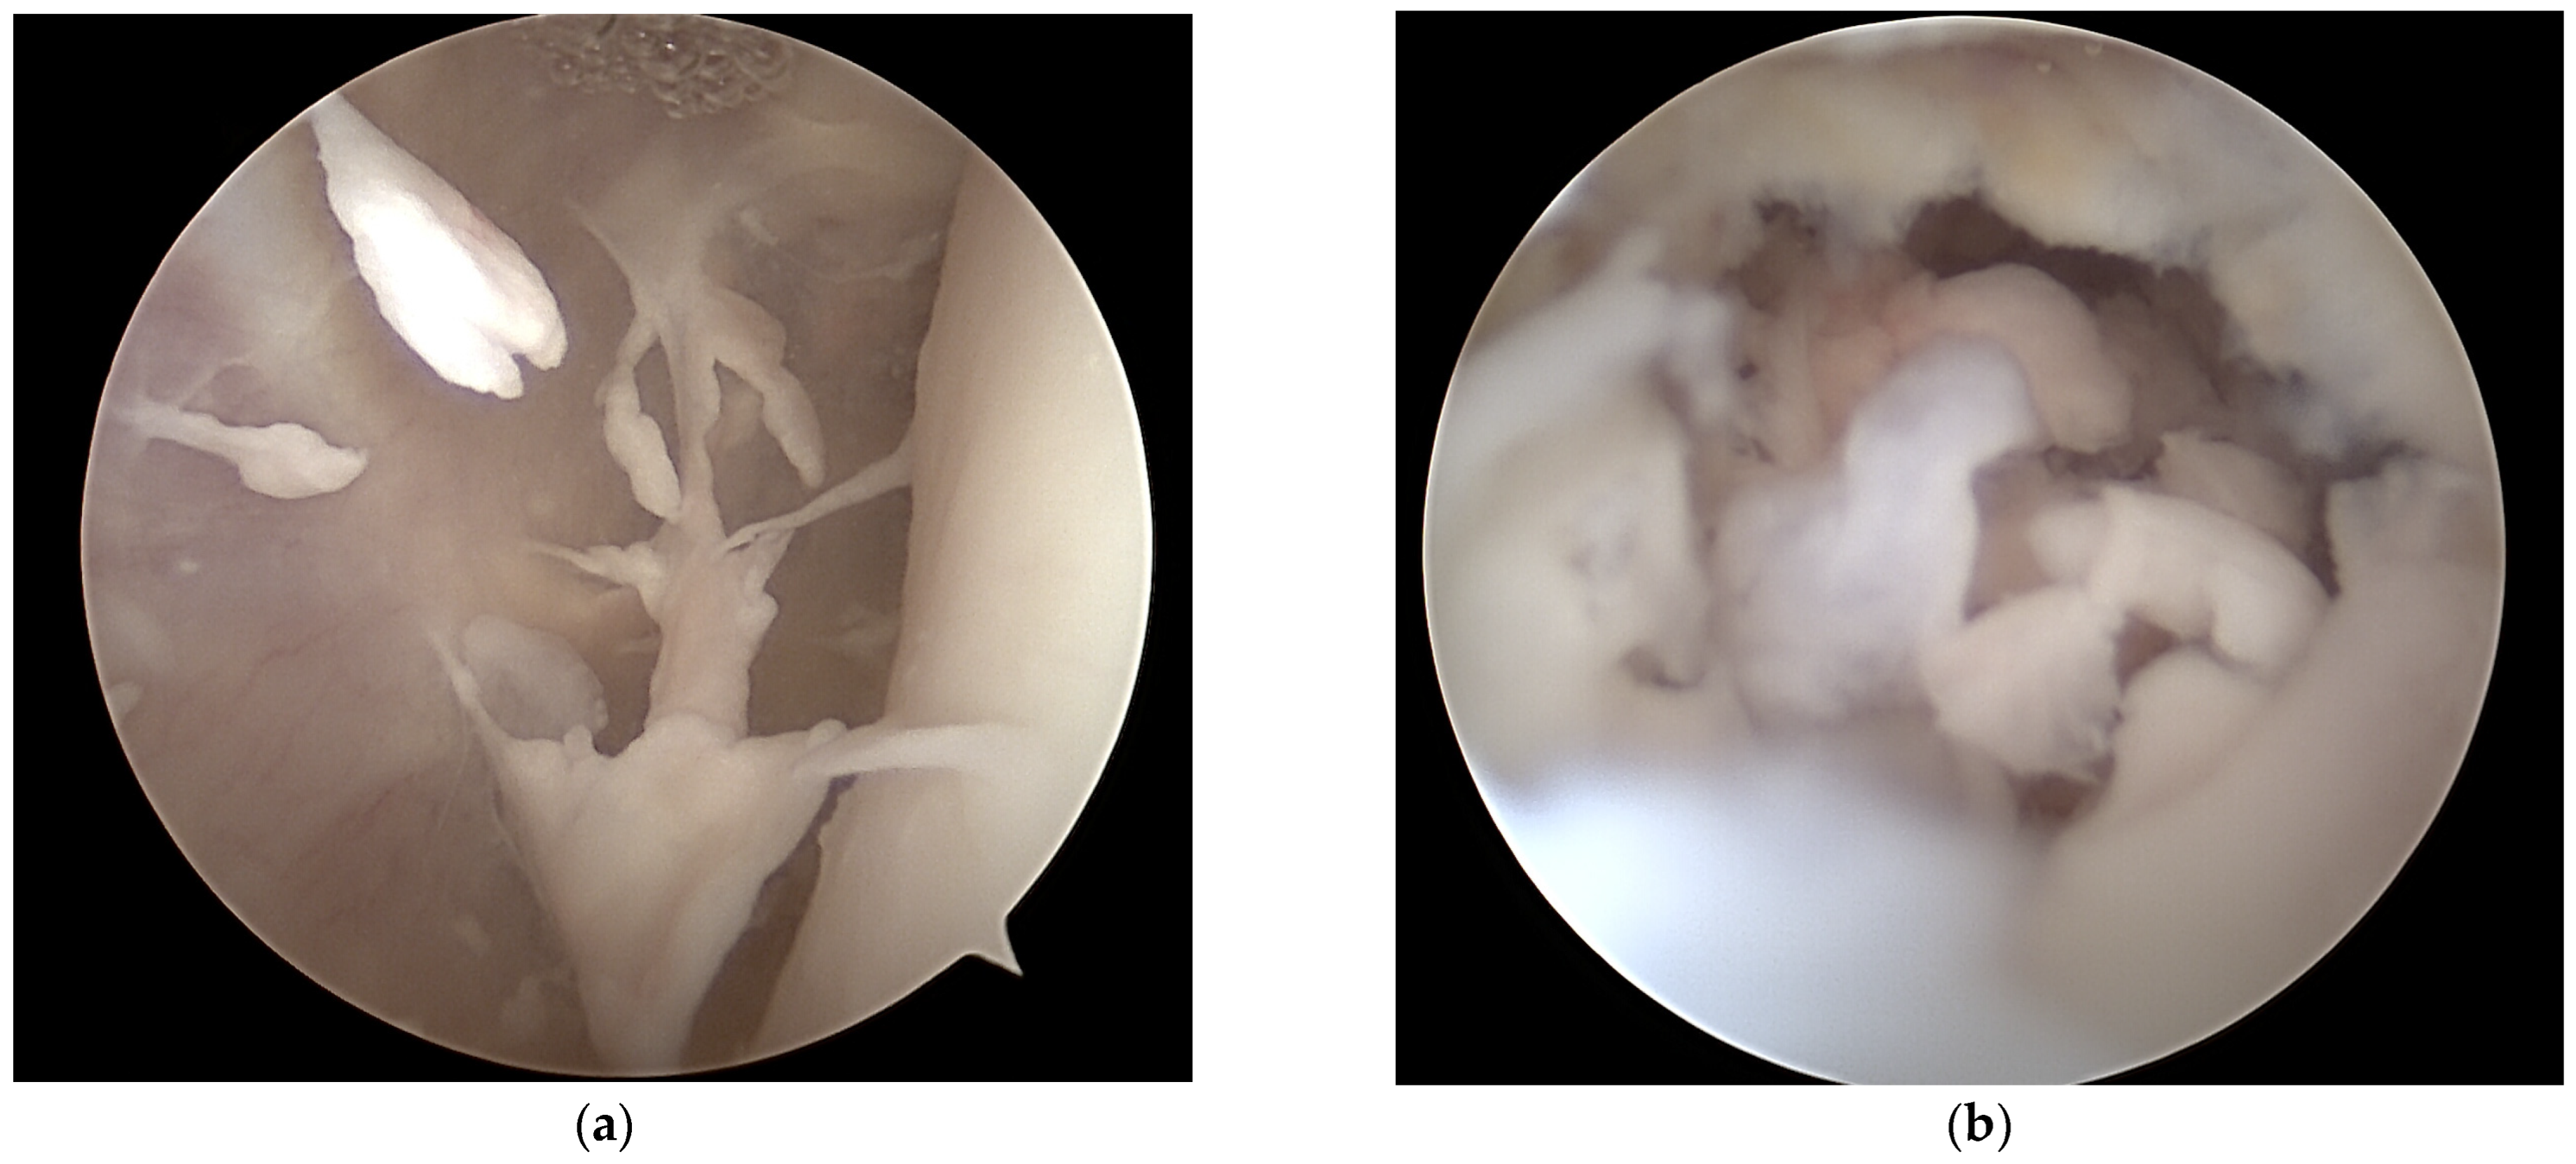

Surgical Management of an Osteomyelitis Associated Subchondral Bone Defect in the Pediatric Knee Based on Arthroscopy, “Ossoscopy” and Bone Grafting—A Case Report

2. Case Presentation